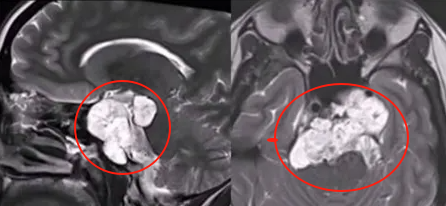

肿瘤情况:于斜坡浸润生长,侵袭骨质,已扩展并侵犯到乙状窦、左侧海绵窦以及从下斜坡至脑干脚间池的硬脊膜部分。侵袭广泛、手术难度倍增、全切十分困难。然而,潇潇是第一次进行手术治疗,如果能在第一次手术时就全切肿瘤,能够最大限度延缓复发,这对潇潇来说极其重要。

在Ⅰ期手术中,福教授采用内镜经鼻入路切除肿瘤的硬膜外部分,成功移除了斜坡和海绵窦区域的肿瘤,这样做能够减少脑脊液泄漏和神经血管损伤的风险。活检结果也证实了是典型的脊索瘤。针对硬膜内部分的肿瘤,则需要等待Ⅱ期手术再进行广泛切除。